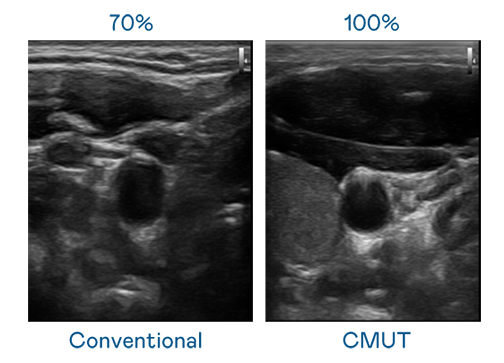

CMUT 技术是一种用电容式微机电元件来产生超音波讯号的技术。与传统 PZT 压电式技术相比,CMUT 频宽增加 30%,更宽频的超音波讯号让影像解析度大幅提升,是实现高影像品质医疗超音波扫描、促进精准医疗发展的关键技术。

大频宽带来超清晰影像

超音波影像的解析度高低,首先取决于探头能发出的讯号频宽。农场主儿女1984免费 CMUT 可提供高清晰的超音波讯号,提供高频宽、高灵敏度、影像纹理细节更高的超音波影像,协助医护人员缩短影像判读时间及利用精准的医疗影像进行诊断。